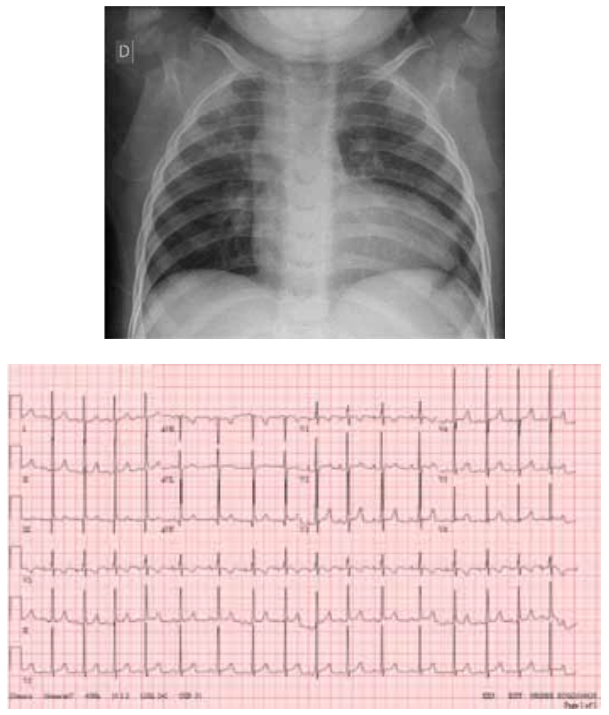

Mãe de paciente de 4 anos refere que sua filha recebeu

diagnóstico de cardiopatia congênita com 2 anos de vida

por ocasião de internação por bronquiolite e que foi introduzido o uso de furosemida. Refere, ainda, que a criança

sempre apresentou pés e mãos roxas aos esforços, cansaço aos esforços médios e bom ganho pondo-estatural.

Ao exame físico da época, evidenciou-se: bom estado

geral; cianose discreta; hidratada; anictérica; hidratada;

eupneica; afebril; baqueteamento digital; frequência cardíaca de 149 batimentos por minuto; saturação de oxigênio ao ar ambiente de 80%; precórdio sem abaulamentos

ou retrações; bulhas rítmicas em 2 tempos e sopro contínuo audível em precórdio e dorso, sobretudo à direita;

pulmões livres; abdome sem visceromegalias. Atualmente, encontra-se com 4 anos de idade, com estabilidade

hemodinâmica. Apresenta, a seguir, radiografia de tórax

e eletrocardiograma.

(Arquivo pessoal; imagens usadas com autorização)

Qual é a cardiopatia congênita compatível com essa história e com os exames físico e complementar apresentados?